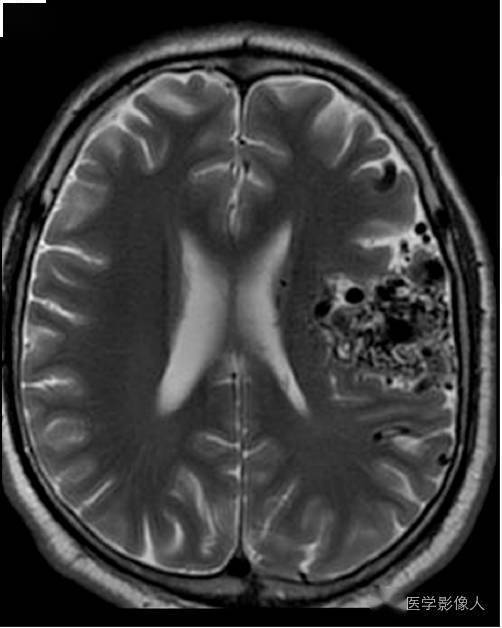

一例淀粉样血管病伴有左侧局灶性表面铁沉积症(箭头所示)患者头颅